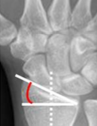

Inclinacion radial promedio

23° (13-30°)

Inclunacion palmar/volar promedio

11° (11-14°)